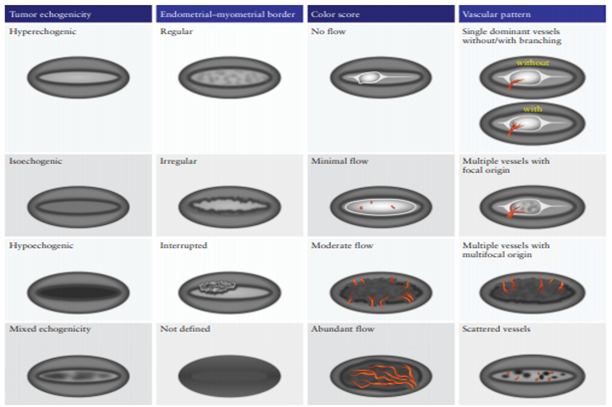

Ultrasonography was conducted in a lithotomy position with an empty bladder. The ultrasound device initially zoomed in on the uterus in a mid-sagittal section for clearer visualization, evaluating the uterus from horn to horn (lateral to lateral wall) and in transverse cross-section from cranial to caudal. The subjective 2D assessment of myometrial and cervical invasion followed the International Endometrial Tumor Analysis IETA Terminology, considering tumor echogenicity, endometrial-myometrial junction, color Doppler result, and vascular pattern (Figure1).

Figure 1. Schematic diagram summarizing morphological and Doppler features according to IETA terminology (18).

Tumor echogenicity can be isoechoic, hypoechoic, heterogeneous and hyperechoic.

Endometrial myometrial junction can be regular, irregular, interrupted or undefined.

Color Doppler: no flow, minimal flow, moderate flow, abundant flow.

Vascular pattern: single blood vessel with or without laceration, multiple blood vessels of focal origin, multiple blood vessels of multifocal origin, scattered blood vessels(Pictures 1-6).